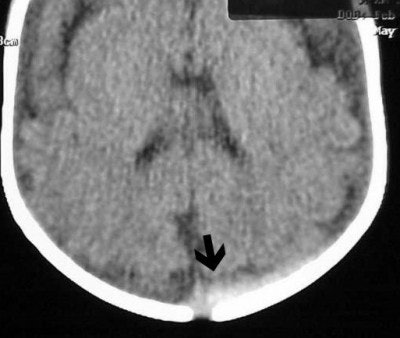

As for blunt-force trauma, say you have a child who is a suspected victim of child abuse (non-accidental trauma). Doctors are looking for an inter-cerebral bleed but nothing is obvious on the axial scan. Are there alternatives?

If the c-spine is cleared, then extend the child’s head as in a reverse coronal position (Figure CT 3). If the c-spine is not cleared, then you can affix the child to a backboard and tilt the foot of the board up about 30°-45° or so. Scans through the brain, if positive, will show blood collecting in the superior convexity (Figure CT 4), an almost definite sign of non-accidental trauma.

![]() |

| Figure CT 4 |